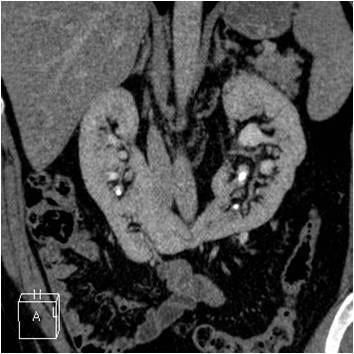

Raphaëlle Renard-Penna, La Revue du Praticien Tomodensitométrie avec injection au temps mixte néphrographique et excrétoire. Reins lithiasiques en fer à cheval.